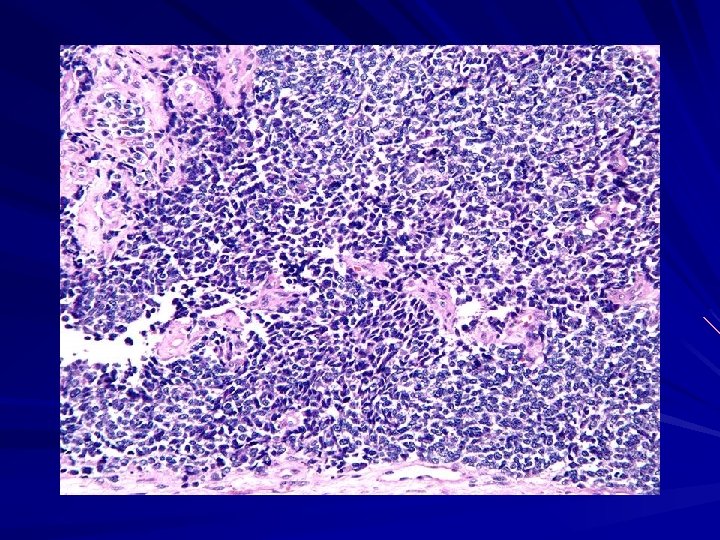

Gross: This Th tumor has a soft, lobulated, white to tan appearance. Micro: sheets of blue cells are regular, and round molded nuclei and a moderate amount of eosinophilic cytoplasm. Blue round cells